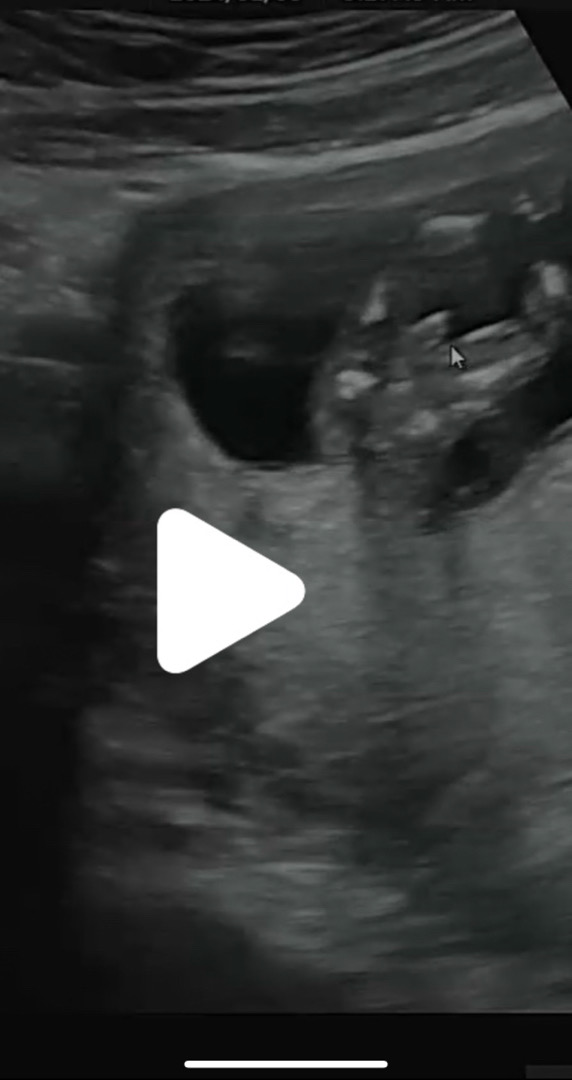

1차2차기형아검사후 다운증후군 고위험군으로 나와서 니프티검사까지했어요~ 주위에 니프티검사까지 한지인은 한명도없다보니 맘이더안좋고 이틀동안 기분이오락가락 주위에서 괜찮을거다했지만~ 그말은 들리지않았는데 오늘드디어괜찮다는결과를 듣고 처음으로글을적어보네요~!❤️ 기분좋은날 우리용용이 딸의로망이있었는데..아들인거죠~ㅋㅋ 모든용띠맘들 화이팅해요~😍😍